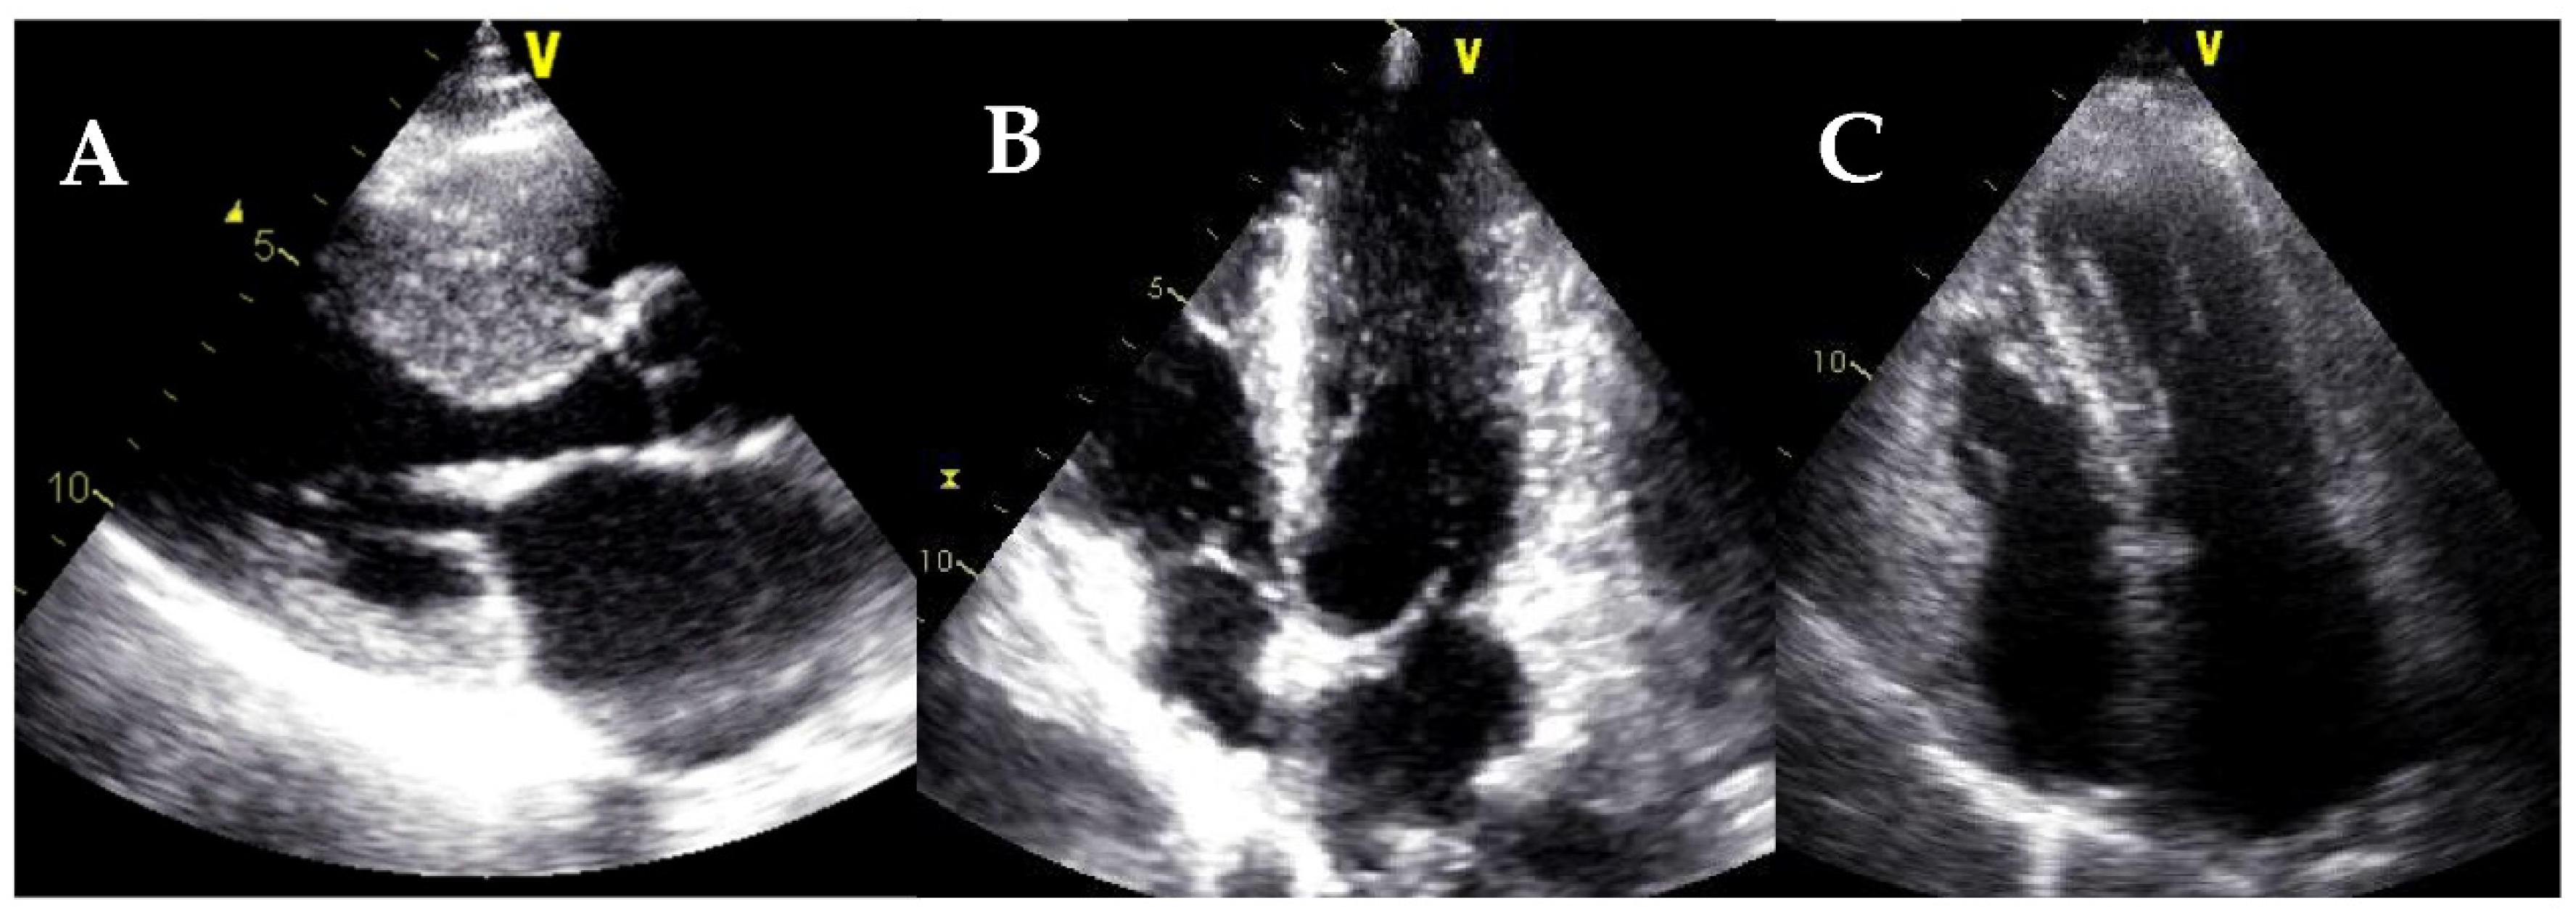

6. Left Ventricular Noncompaction